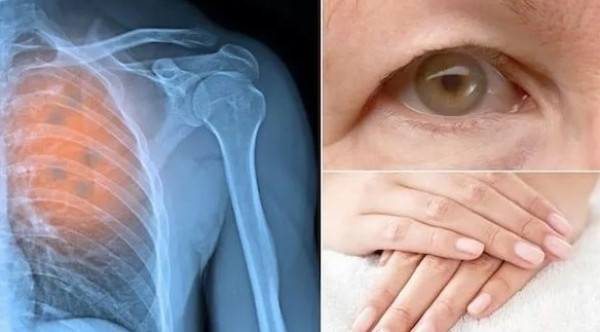

منها السعال المستمر.. 5 علامات تحذيرية للسرطان

يعتبر مرض السرطان له أنواع عديدة وأعراض كثيرة، ولكن كثيرين يتجاهلون هذه الأعراض التي قد تنذر بالإصابة بهذا المرض مع أن الفحوص المبكرة والمنتظمة تزيد فرص الشفاء.

إليك 5 أعراض لا ينبغي تجاهلها، وفق (الجزيرة نت).

يكون السعال عادة مصحوبًا بنزلة برد أو تأثير شبيه بالإنفلونزا ولا داعي للقلق في البداية، غير أنه على أي شخص يعاني السعال المستمر الخضوع لفحص أكثر دقة، كما تشرح تيريز بارثولوميو من مركز الوقاية من السرطان أنه في معظم الأحيان، السعال لا يعني السرطان، لكنه ينبغي فحص السعال المستمر لمعرفة ما إذا كان يمكن أن يكون ذلك علامة على سرطان الرئة

يمكن أن يكون للحموضة المعوية عدد من الأسباب، منها الإجهاد المفرط أو اتباع نظام غذائي يحتوي على نسبة عالية من الدسم والسكر، فإذا ظهرت الأعراض من حين إلى آخر فقط ، فلا داعي للقلق، لكن حرقة المعدة المستمرة يمكن أن تكون مؤشرًا على الإصابة بسرطان الحلق والحنجرة.

يُقلّل غالبًا من الخطر الذي يمكن أن تشكله الشامة، إذ يمكن أن تتطور إلى سرطان الجلد، وهناك علامات على ذلك منها حكة مستمرة أو حرقان في المنطقة المصابة، فإن لاحظ الشخص مثل هذه الأعراض، فيُنصح بزيارة طبيب الأمراض الجلدية.

ويمكن أن يكون للدم في البراز أسباب كثيرة ومعظمها يشير إلى حالات حميدة أكثر من السرطان، غير أن بعض الأسباب الرئيسة هي البواسير أو التمزقات الصغيرة في البطانة، حيث يوصي المتخصصون بضرورة إجراء فحص سنوي للبراز للأشخاص من عمر 50 عامًا فما فوق.

يمكن أن يكون تورم الغدد الليمفاوية غير المؤلمة مؤشرًا على الإصابة بسرطان الغدد الليمفاوية، خاصة إذا استمر هذا التورم غير المؤلم مدة طويلة ولم يختف مرة أخرى؛ لذلك يوصى بإجراء فحص طبي.

و يعتبر الطب اليوم بنسب شفاء عالية أو على الأقل سنوات مديدة خالية من الأعراض الجانبية بالنسبة لمعظم أنواع السرطانات، لكن الأهم هو الخضوع للفحوص المبكرة والمنتظمة عند ظهور الأعراض.